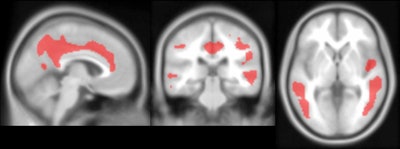

The researchers found significant levels of reduced FDG uptake (hypometabolism) with increases of beta amyloid, which could indicate brain atrophy. The most significant declines in FDG uptake (p < 0.05) were observed in the perinatal cortex, precuneus, and posterior cingulate, which typically are associated with early-stage Alzheimer's.

Conversely, the authors noted significant FDG uptake (hypermetabolism) with greater beta-amyloid load, with the most significant increases (p < 0.05) in the putamen and thalamus. All of the changes in FDG were driven entirely by subjects who were beta-amyloid-positive.

PET images show significant negative associations between PiB and FDG in the cingulate, temporal cortex, parietal cortex and precuneus. Image set courtesy of Journal of Nuclear Medicine (JNM, May 1, 2020; vol. 61: Supplement 1).

PET images show significant negative associations between PiB and FDG in the cingulate, temporal cortex, parietal cortex and precuneus. Image set courtesy of Journal of Nuclear Medicine (JNM, May 1, 2020; vol. 61: Supplement 1).As for the striatum and early signs of Alzheimer's disease in Down syndrome subjects, FDG reductions were observed in the caudate but were not statistically significant (p = 0.53). The FDG decrease "strongly correlated with ventricle volume," Zammit added, "suggesting that the FDG reduction may be influenced by ventricular enlargement that is common in Down syndrome with Alzheimer's disease."